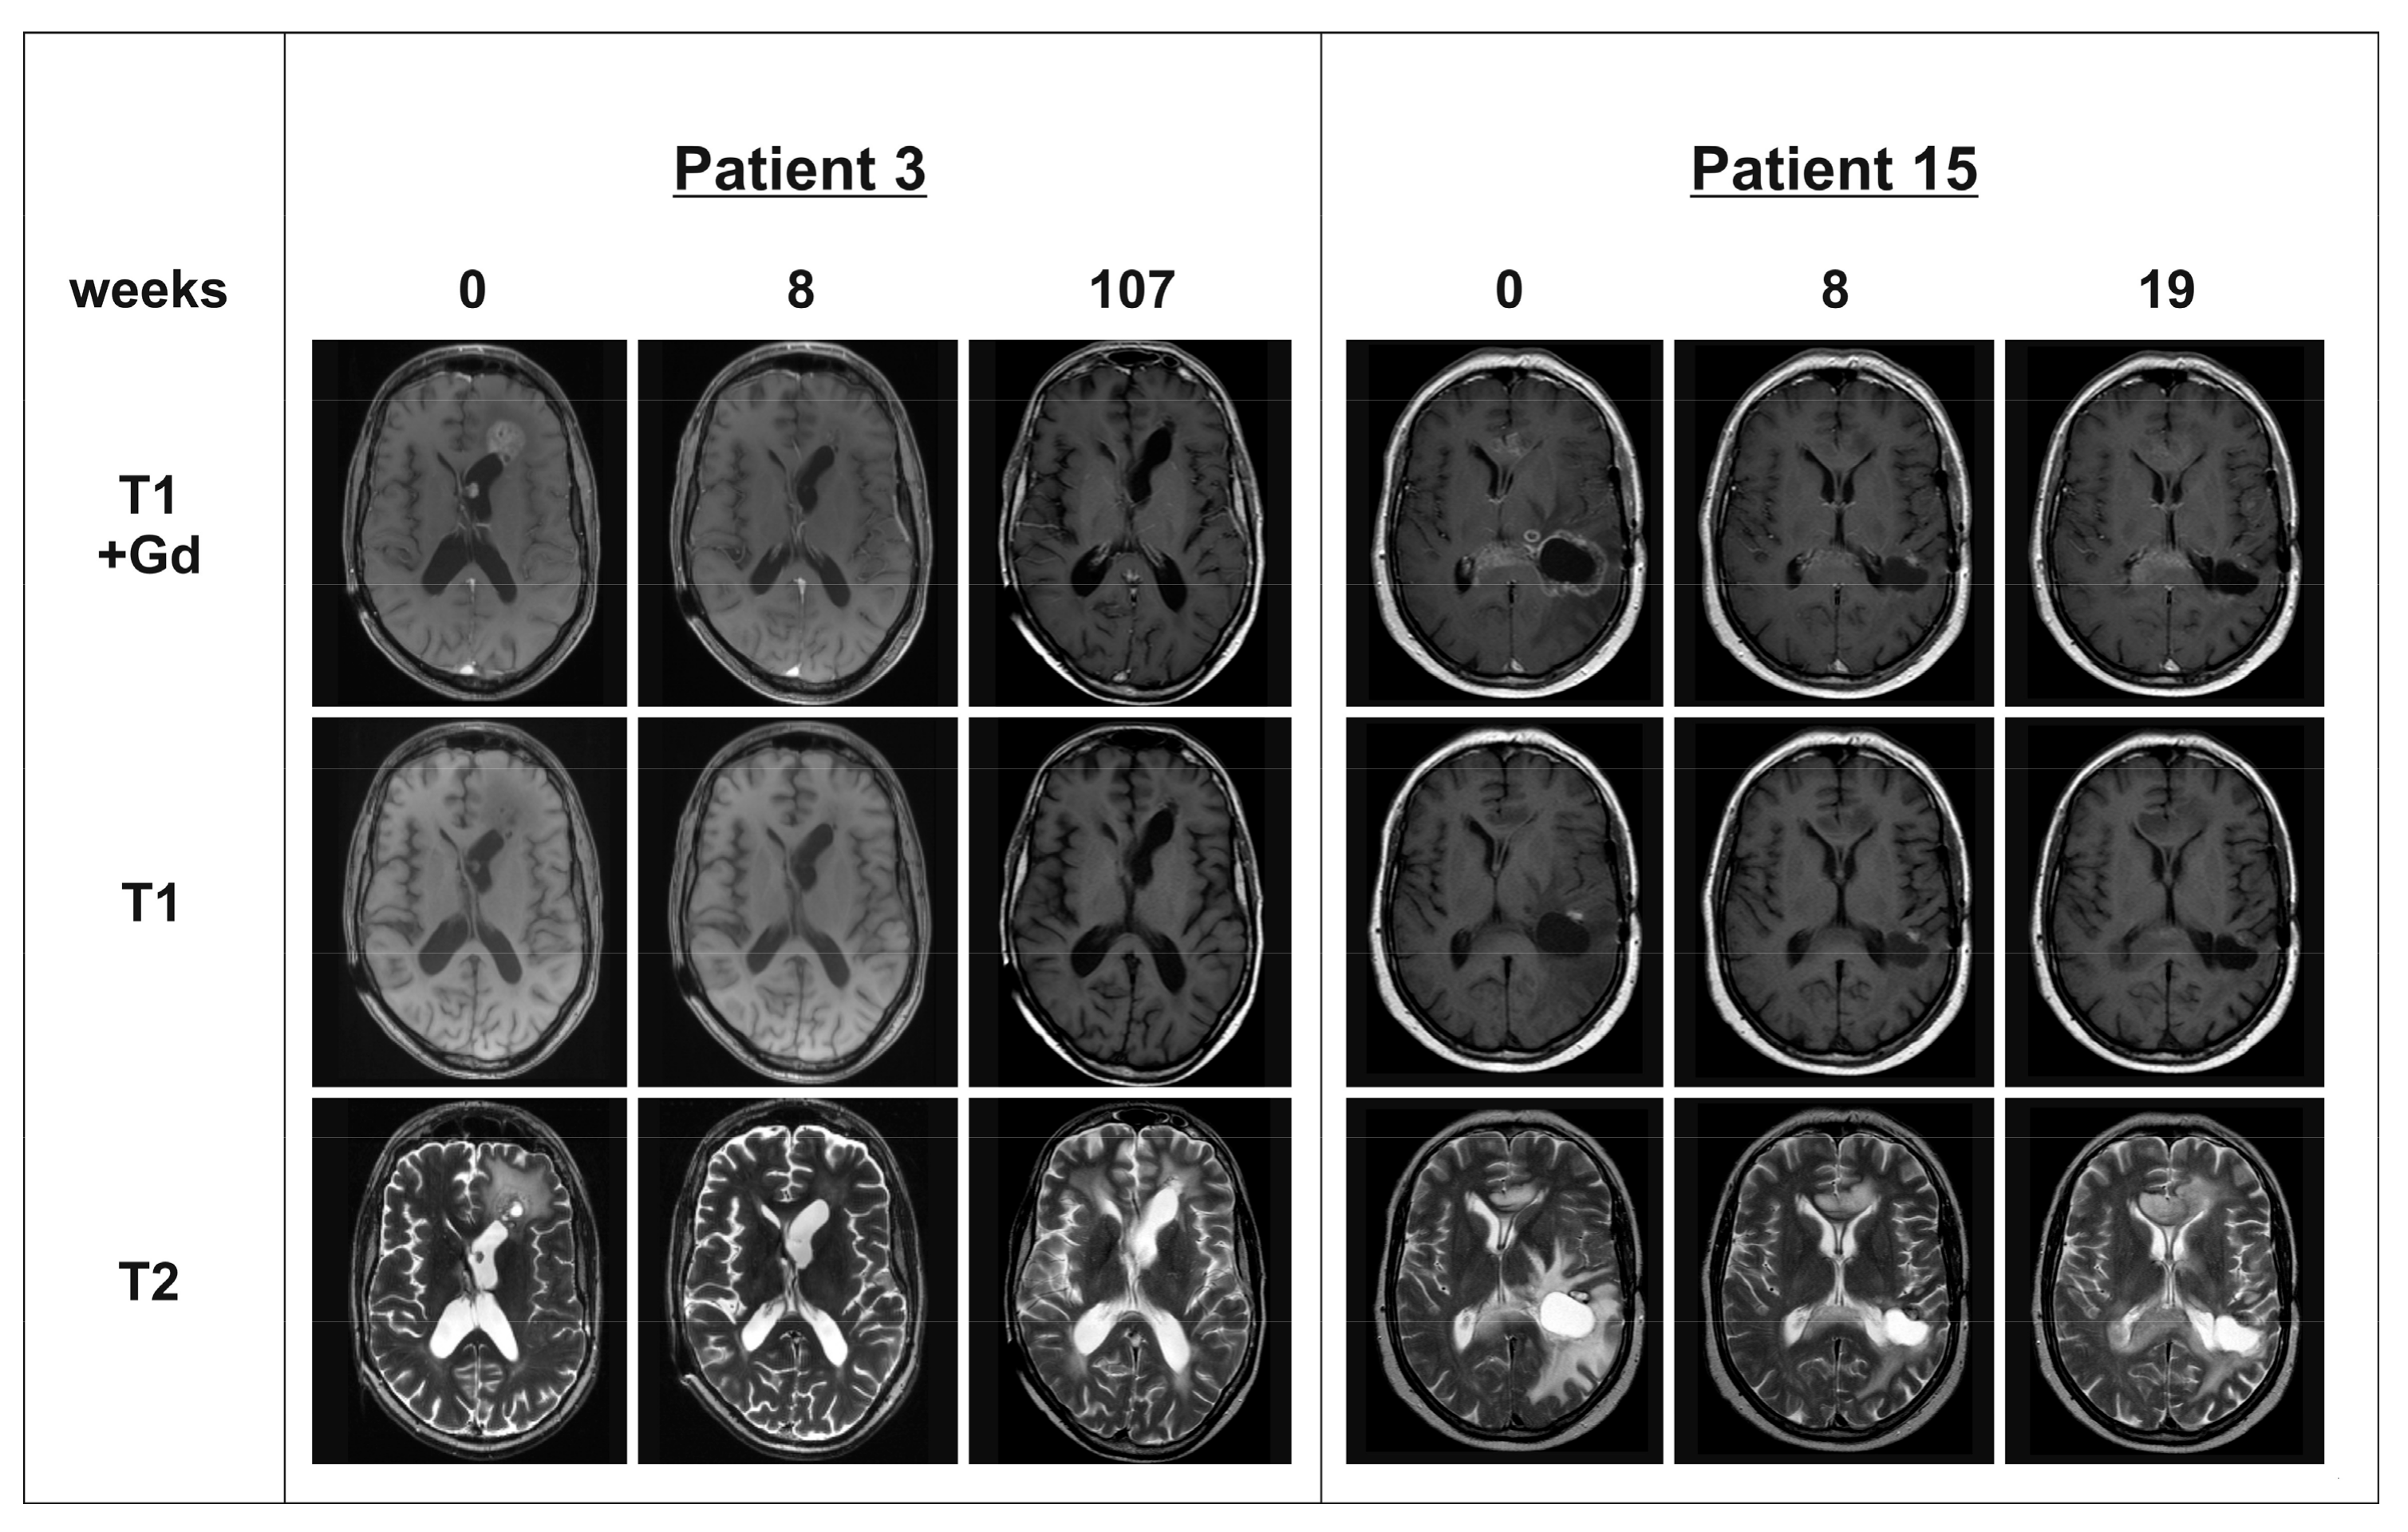

Figure 2. Progression-free survival (PFS) and overall survival (OS). No significant difference from patients with multifocal glioblastomas (mfGB) compared to patients with solitary glioblastomas (sGB) was observed. However, there was a clear trend for worse OS in patients with mfGB (p = 0.19).

In the patient group with mfGB, we observed as best response a partial response (PR) in 11 patients, stable disease (SD) in two patients, mixed response (MR) in one patient, and progressive disease (PD) in two patients (see Table 1 and Figure 1). In the sGB matched control cohort, best response was PR in nine patients, SD in three patients, MR response in one patient, and PD in three patients (see Table 2). There was no significant difference in PFS and OS between patients with mfGB and sGB. However, there was a clear trend for shorter OS in mfGB as compared to sGB (see Figure 2). Median PFS was 21 weeks for patients with mfGB, and 23.5 weeks for their matched controls with sGB. Median OS was 33 weeks in the mfGB group, and 43.5 weeks in the sGB group. One patient in each group was still alive at the time of data analysis (patient 3 at week 313 and patient C16 at week 129). In the mfGB group, Karnofsky performance score (KPS) improved after initiating BEV therapy in five patients, stabilized in 10 patients, and deteriorated in one patient. In the matched control group of sGB patients, KPS improved in four patients, stabilized in 10 patients, and deteriorated in two patients. In the mfGB group, steroid intake was reduced after BEV therapy initiation in 13 patients and was left untouched in three patients. In no mfGB patient did the steroid dose have to be increased. In the sGB control cohort, steroid intake was reduced in 12 patients, left unchanged in three patients, and had to be escalated in one patient. To evaluate if the tumors developed an even more infiltrative phenotype under BEV therapy, we explored the share of new lesions (T1 contrast enhancing separated by at least 1 cm from existing lesions) on the last magnetic resonance imaging (MRI) showing progression before the start of BEV therapy and at progression under BEV therapy. In the mfGB goup, new lesions were observed in 40% prior to BEV therapy initiation and in 23.1% of the relapses under BEV therapy (p = 0.36). In the sGB control cohort, new lesions occurred in 31.3% prior to and in 21.4% under BEV therapy (p = 0.56; see Table 3). There was no significant difference in the frequency of new lesions between the mfGB and sGB groups (p = 0.62 prior to BEV therapy; p = 0.92 under BEV therapy).

This patient series shows that clinical response on BEV treatment is similar in patients with mfGB as compared to sGB. Response rates, clinical improvement, and the rate of steroid reduction were similar in both groups. In particular, PFS was similar in patients with mfGB as compared to the matched control patients with sGB. There was, however, a trend for a shorter OS in the patients with mfGB. This was not unexpected, as several large studies have shown that BEV therapy does not improve OS [17,19,20] and mfGB per se have a more unfavorable prognosis [3,5]. Therefore, even provided that BEV has a similar effect in mfGB and sGB, OS cannot be expected to be comparable in the two groups. In both the mfGB and sGB groups, we did not observe the development to a more invasive phenotype as measured by the frequency of appearance of new lesions on MRI under BEV therapy. There was even a trend for fewer new lesions both in mfGB and sGB under BEV therapy, which did not reach significance. Comparably, BEV therapy did not result in a more invasive growth pattern in glioma patients with a gliomatosis cerebri growth pattern or leptomeningeal metastases [21,22].